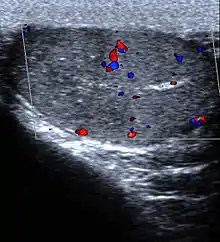

| Diagnostic method | Ultrasound, urine tests, blood tests[1][2] |

Ultrasound is useful if the cause is not certain based on the above measures.[15] If the diagnosis of torsion is certain, imaging should not delay definitive management such as physical maneuvers and surgery.[7]